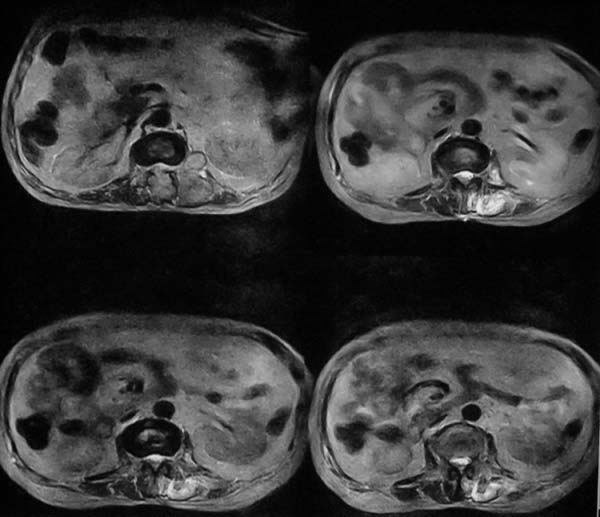

病史特点:

1.中年男性

2.腰疼,双下肢麻木1月。

3.ct 可右肾上腺占位,腰1椎体及附件可见骨质破坏及软组织肿块。

4.mri:腰1椎体及附件t1wi低信号,t2wi高信号。

考虑右侧肾上腺癌骨转移.或右肾上腺及骨均为转移瘤。